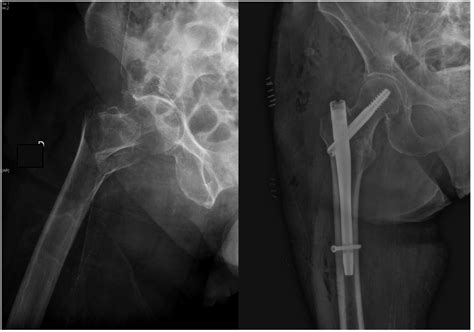

The Trochanteric Fixation Nail (TFN) is a type of intramedullary nail used primarily for the treatment of intertrochanteric and subtrochanteric fractures of the femur. These fractures are common in elderly patients, often resulting from falls or other traumatic events. The TFN is designed to provide stable fixation, allowing for early mobilization and rehabilitation.

1. Preoperative Planning: Detailed imaging, such as X-rays or CT scans, is used to assess the fracture pattern and plan the surgical approach.

4. Nail Insertion: The TFN is inserted into the medullary canal of the femur, crossing the fracture site.

5. Proximal Locking: Proximal locking screws are placed to secure the nail in the femoral head and neck.

6. Distal Locking: Distal locking screws are inserted to stabilize the nail in the shaft of the femur.

Several case studies and clinical outcomes have demonstrated the effectiveness of the Trochanteric Fixation Nail in treating hip fractures. For example, a study published in the Journal of Orthopaedic Trauma reported high union rates and low complication rates in patients treated with the TFN. Another study highlighted the benefits of early mobilization and reduced hospital stays in patients undergoing TFN surgery.

These studies underscore the clinical efficacy of the TFN and its role in improving patient outcomes.